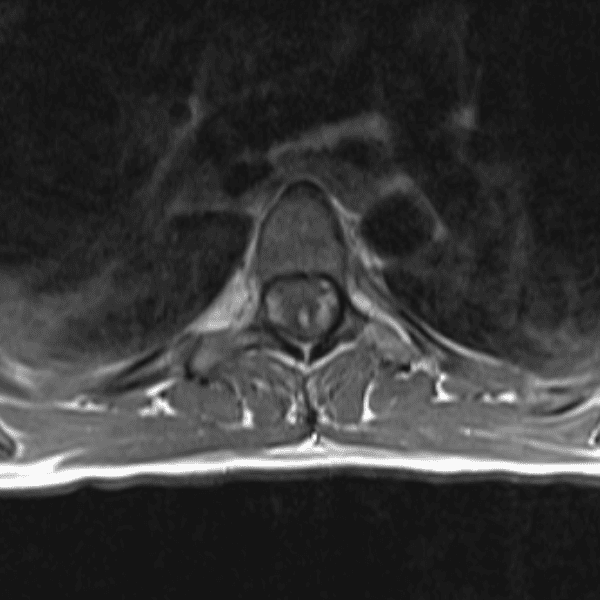

Simulates call by including subtle or difficult cases and some normals.

35 cases